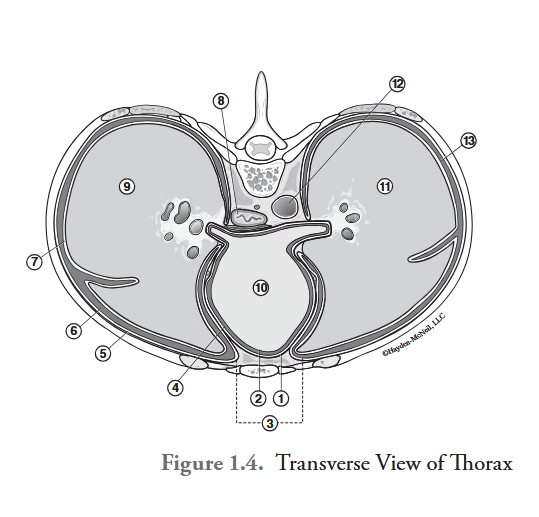

What is labeled #1?

parietal pericardium

What is labeled #2?

visceral pericardium (epicardium)

What is labeled #3?

mediastinum

What is labeled #4?

pericardial cavity

What is labeled #5?

parietal pleura

What is labeled #6?

right pleural cavity

What is labeled #7?

visceral pleura

What is labeled #8?

esophagus

What is labeled #9?

right lung

What is labeled #10?

heart

What is labeled #11?

left lung

What is labeled #12?

descending aorta

What is labeled #13?

left pleural cavity